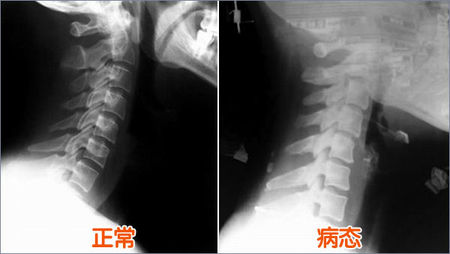

通过X线片上的颈椎显像:沿此曲度走行,在各个颈椎椎体后缘都有形成的连续、光滑的弧形曲线,医学上称之为颈椎曲度。当长时间不正确的坐姿、或是长时间的劳累、颈椎缺少活动、脊柱损伤、脊柱钙化等就会导致颈椎生理曲度变直。

生理曲度存在

生理曲度变直

颈椎生理曲度的存在,能增加颈椎的弹性,减轻和缓冲重力的震荡,防止对脊髓和大脑的损伤。由于长期坐姿、睡姿不良和椎间盘髓核脱水退变时,颈椎的前凸可逐渐消失,甚至可变直或呈反张弯曲,即向后凸,成为颈椎病X线上较为重要的诊断依据之一。